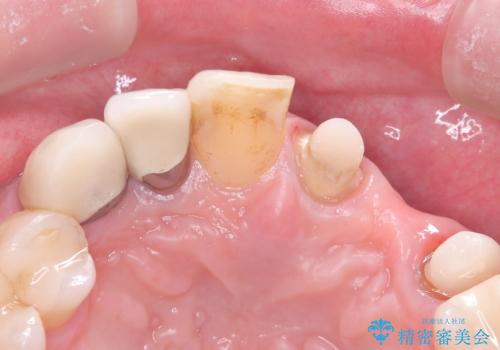

左上1番目~3番目にかけてブリッジの仮歯が入った状態で来院された患者さんで、左上3に縁下カリエスを認め抜歯してインプラントか牽引(エクストリュージョン)を行うか、歯肉根尖側移動術を行うか選択いただき牽引の後補綴処置を行うこととしました。

左上3の牽引を1か月半ほど行った後、補綴治療を行っています。

両支台歯とも根尖病巣は認められなかったため、ファイバ-コアからのやり替えとしました。